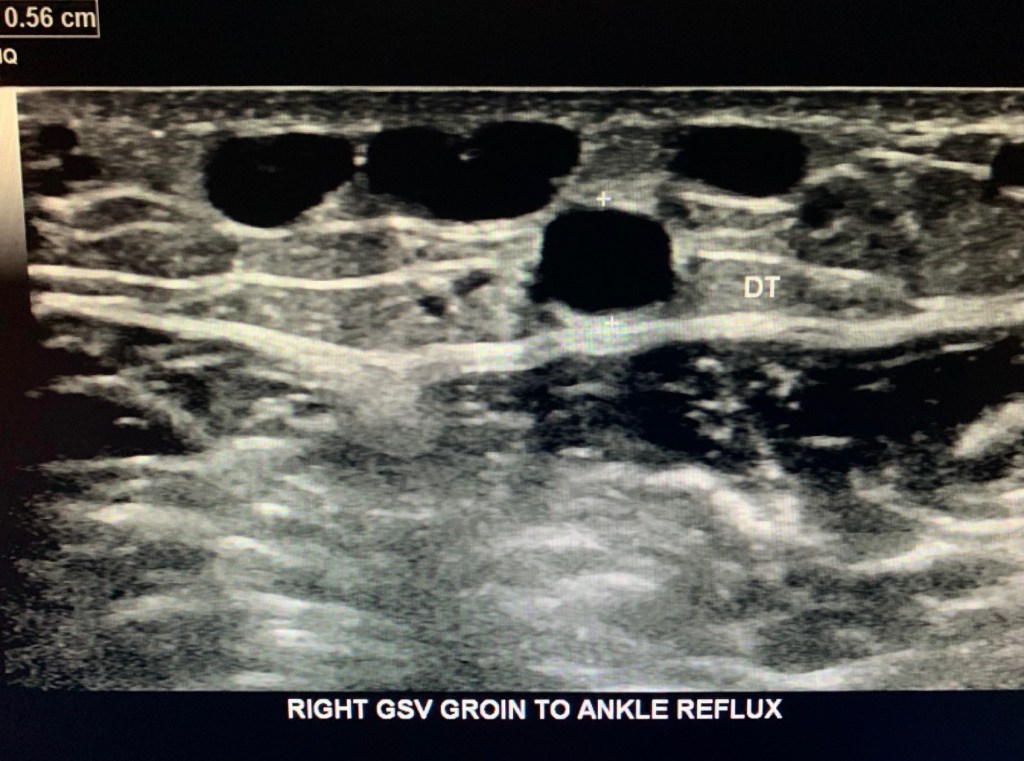

Great Saphenous Vein

Ask if there’s a history of GSV harvesting. The Great Saphenous Vein (GSV) is evaluated next for incompetence.

This patient demonstrated severe venous reflux in the GSV from the groin to ankle.

Measure the diameter of the incompetent GSV areas in transverse.

In this case we measure the entire length (proximal to distal thigh and proximal to distal calf).